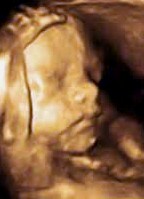

Unser Ultraschallgerät (General Electric Voluson E6) ist ein Hochleistungsgerät mit Sonden für die Untersuchung durch die Bauchdecke (abdominal), durch die Scheide (transvaginal) sowie für die Untersuchung der weiblichen Brust. Ausserdem kann das ungeborene Kind im computermässig generierten, dreidimensionalen Bild (3D) und im bewegten dreidimensionalen Live-Bild (4D) dargestellt werden. Dafür müssen jedoch von der Lage des Kindes her gewisse Voraussetzungen erfüllt sein.

3D-Rekonstruktion der Wirbelsäule